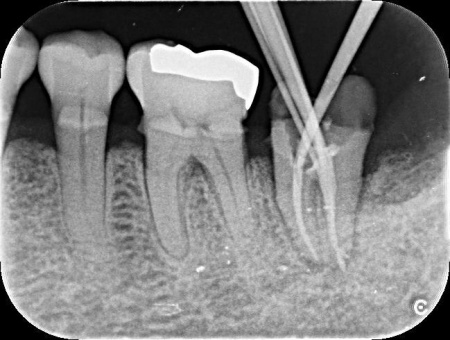

レントゲン撮影をして詳しく拝見したところ、左下奥歯に慢性歯根膜炎が認められました。

根管治療とは、細菌感染した神経を除去して根管を洗浄・消毒し、薬を詰める治療方法です。

今回は、殺菌効果の高いMTAセメントを用いて根管をしっかりと封鎖することをお伝えし、治療に同意いただきました。

まずは左下奥歯に根管治療を行い、MTAセメントを用いて根の先端まで隙間なく封鎖します。

その後、被せ物を装着するために歯の形を整え、型取りを行いました。